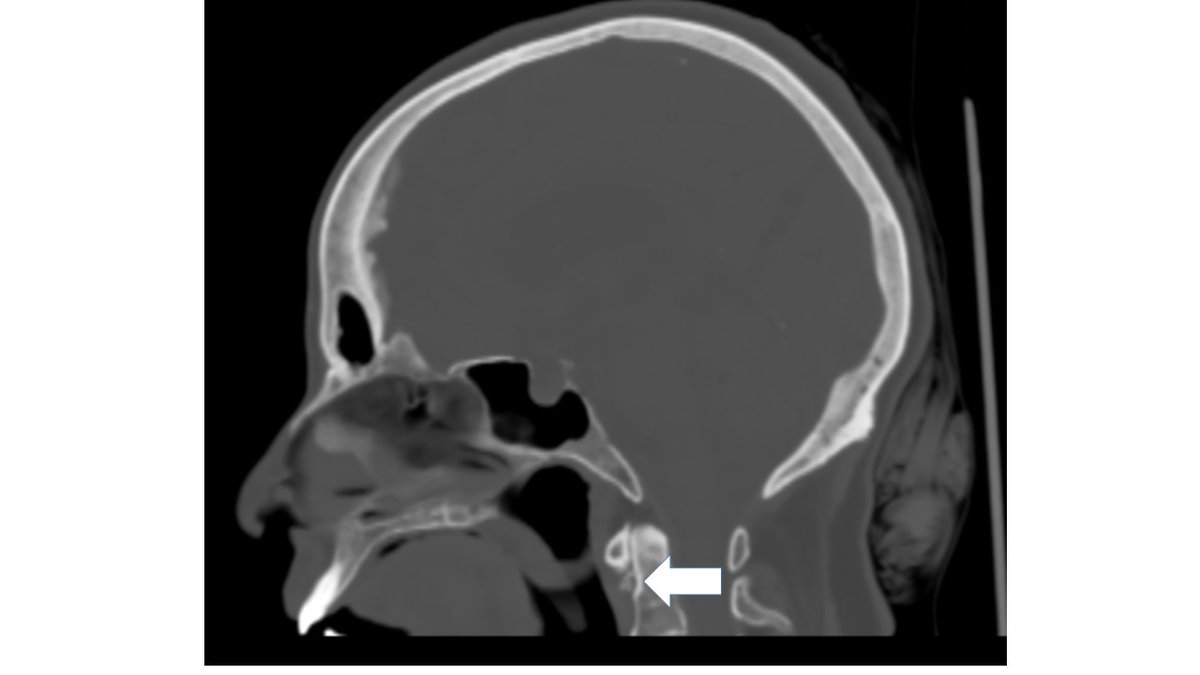

A 71-year-old man presented to us with right-sided headache after a flight. Immediately after ascent, he developed severe right eye pain and headache and lost consciousness.